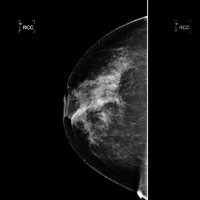

Scientists have pinpointed a key cancer-causing gene that, when overactive, triggers a particularly aggressive type of breast cancer to develop. This is the first time in over five years that scientists have discovered a new breast cancer 'oncogene' - cancer-causing genes that when overactive upset the normal checks and balances that control when and how often a cell divides. The researchers, based at Cancer Research UK's Cambridge Research Institute at the University of Cambridge and at the British Columbia Cancer Agency in Vancouver, Canada, believe testing patients tumours to see if the gene - called 'ZNF703' - is overactive could help identify patients with more aggressive tumours, so their treatment can be tailored accordingly. The research is published in the journal EMBO Molecular Medicine today (Friday, 18 February) alongside a study from an independent research group identifying the same gene, providing definitive evidence that ZNF703 is a genuine breast cancer oncogene. It's thought that up to a third of more aggressive oestrogen positive breast cancers could have multiple copies of the ZNF703 gene. If this is confirmed in larger studies it could pave the way for the development of cancer treatments specifically targeting ZNF703. Testing for ZNF703 activity in the tumour could help reveal if patients are likely to respond to such drugs, in the same way that testing for Her2 activity is used to reveal if a patient may benefit from Herceptin.